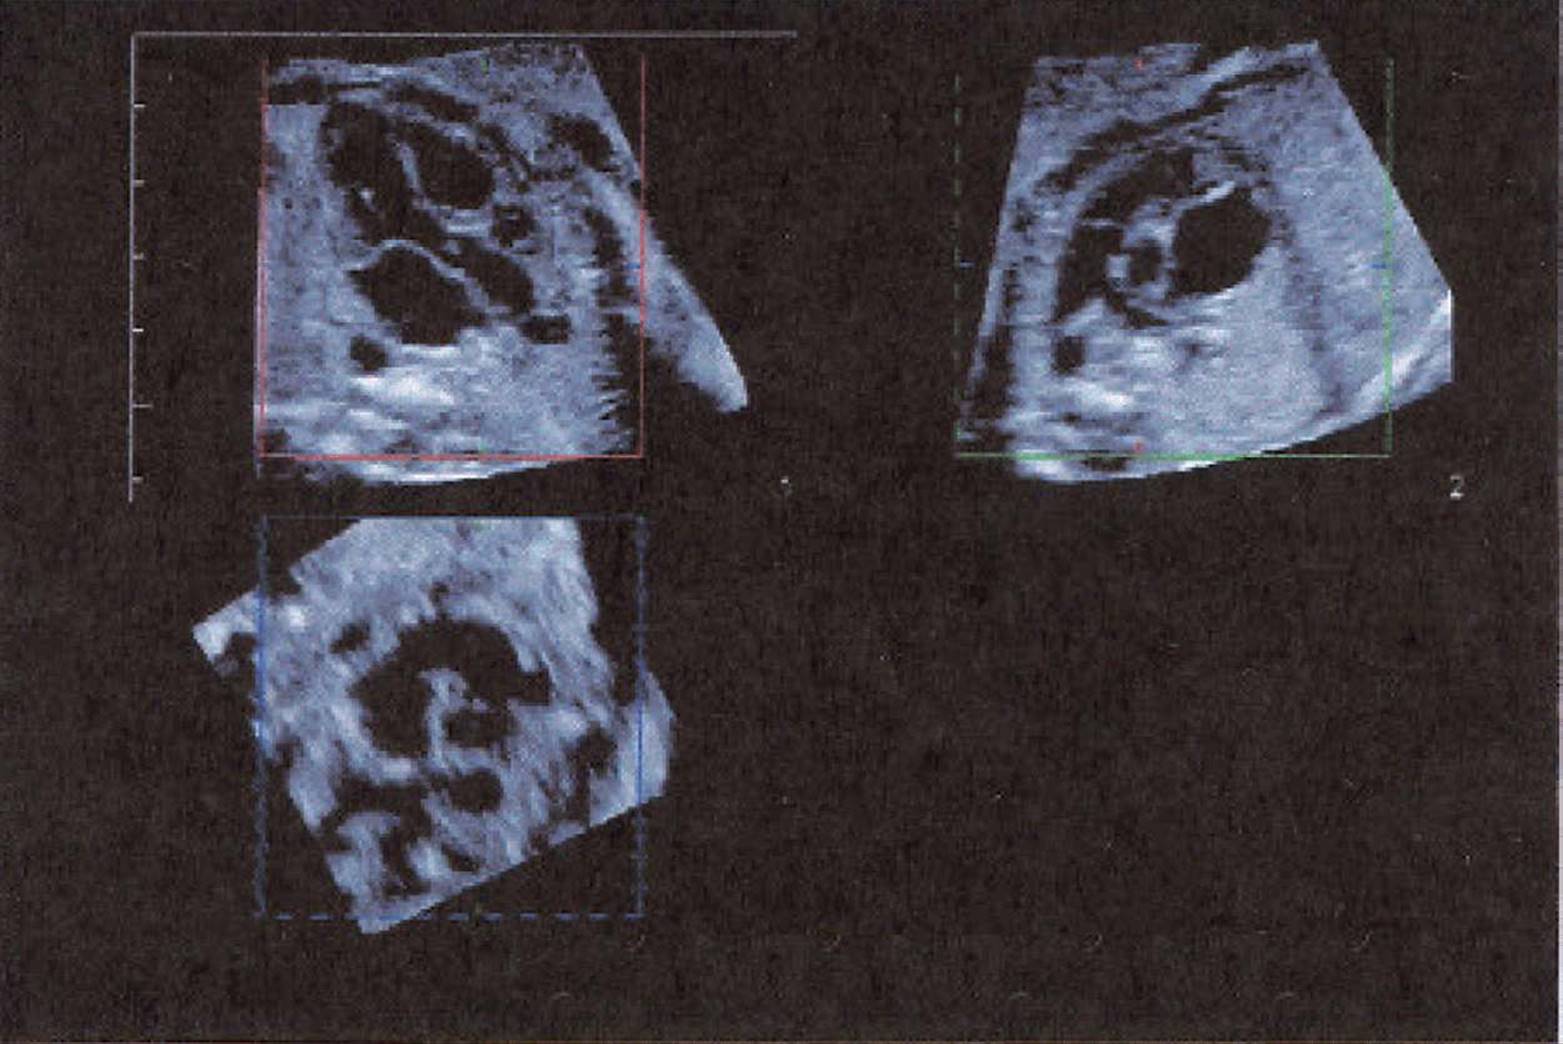

FIGURE 8–16. Spatial, temporal image correlation (STIC) of normal fetal ventricles/atria and outflow tracts. (Courtesy of Philips Healthcare.)

Three-dimensional sonography is particularly useful in the evaluation of the fetal heart. This is due to the ability to depict selected scan planes that may not be obtainable on 2D. The heart volume can be obtained with special software that affords spatial, temporal image correlation (STIC). This technique allows for systematic evaluation of cardiac structures regardless of fetal position.